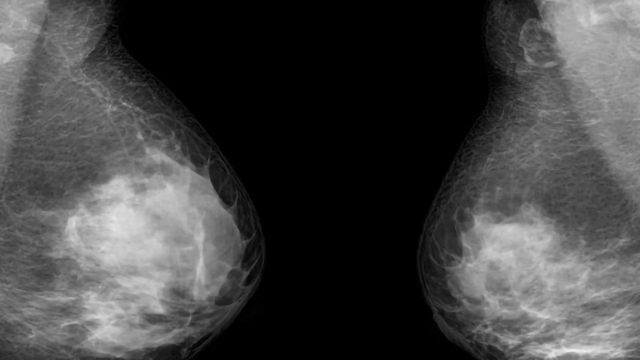

血液测试检测16 18乳腺癌复发的病例

一个简单的血液检测乳腺癌复发提出容易监测病人的可能性,这将为早期治疗提供一个关键的机会比其他电流测试。